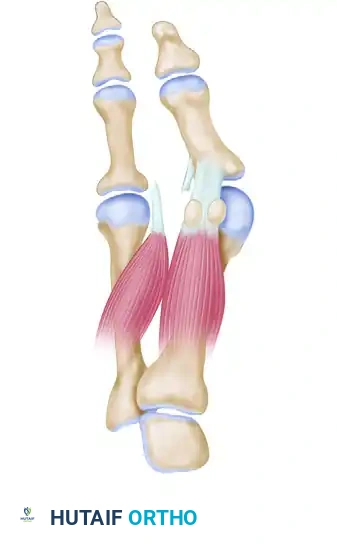

Phase 1: The Distal Soft Tissue Procedure (Lateral Release)

The first incision is made dorsally in the first intermetatarsal space. Its purpose is to release the deforming lateral structures: the adductor hallucis, the deep transverse intermetatarsal ligament, and the lateral capsule of the first MTP joint.

- Adductor Hallucis Release: The adductor hallucis approaches the base of the proximal phalanx obliquely. Once identified, release it completely from its insertion at the base of the proximal phalanx and from the lateral edge of the fibular sesamoid.

- Transverse Intermetatarsal Ligament Release: Release the deep transverse intermetatarsal ligament, which lies plantar to the adductor tendon.

- Sesamoid Apparatus Release: Ensure the deep transverse intermetatarsal ligament attaching to the fibular sesamoid is fully released. This eliminates the deforming force that pulls the sesamoid apparatus laterally from under the metatarsal head.

- Suture Preparation: Retrieve the completely freed adductor hallucis tendon and lift it into the wound. Pass three absorbable 2-0 sutures through the lateral capsule on the first metatarsal head (just proximal to the release), then through the adductor hallucis tendon, and finally through the capsuloligamentous intrinsic tissue on the medial side of the second metatarsal head. Do not tie these sutures yet. Clamp them with hemostats and allow them to rest in the web space.